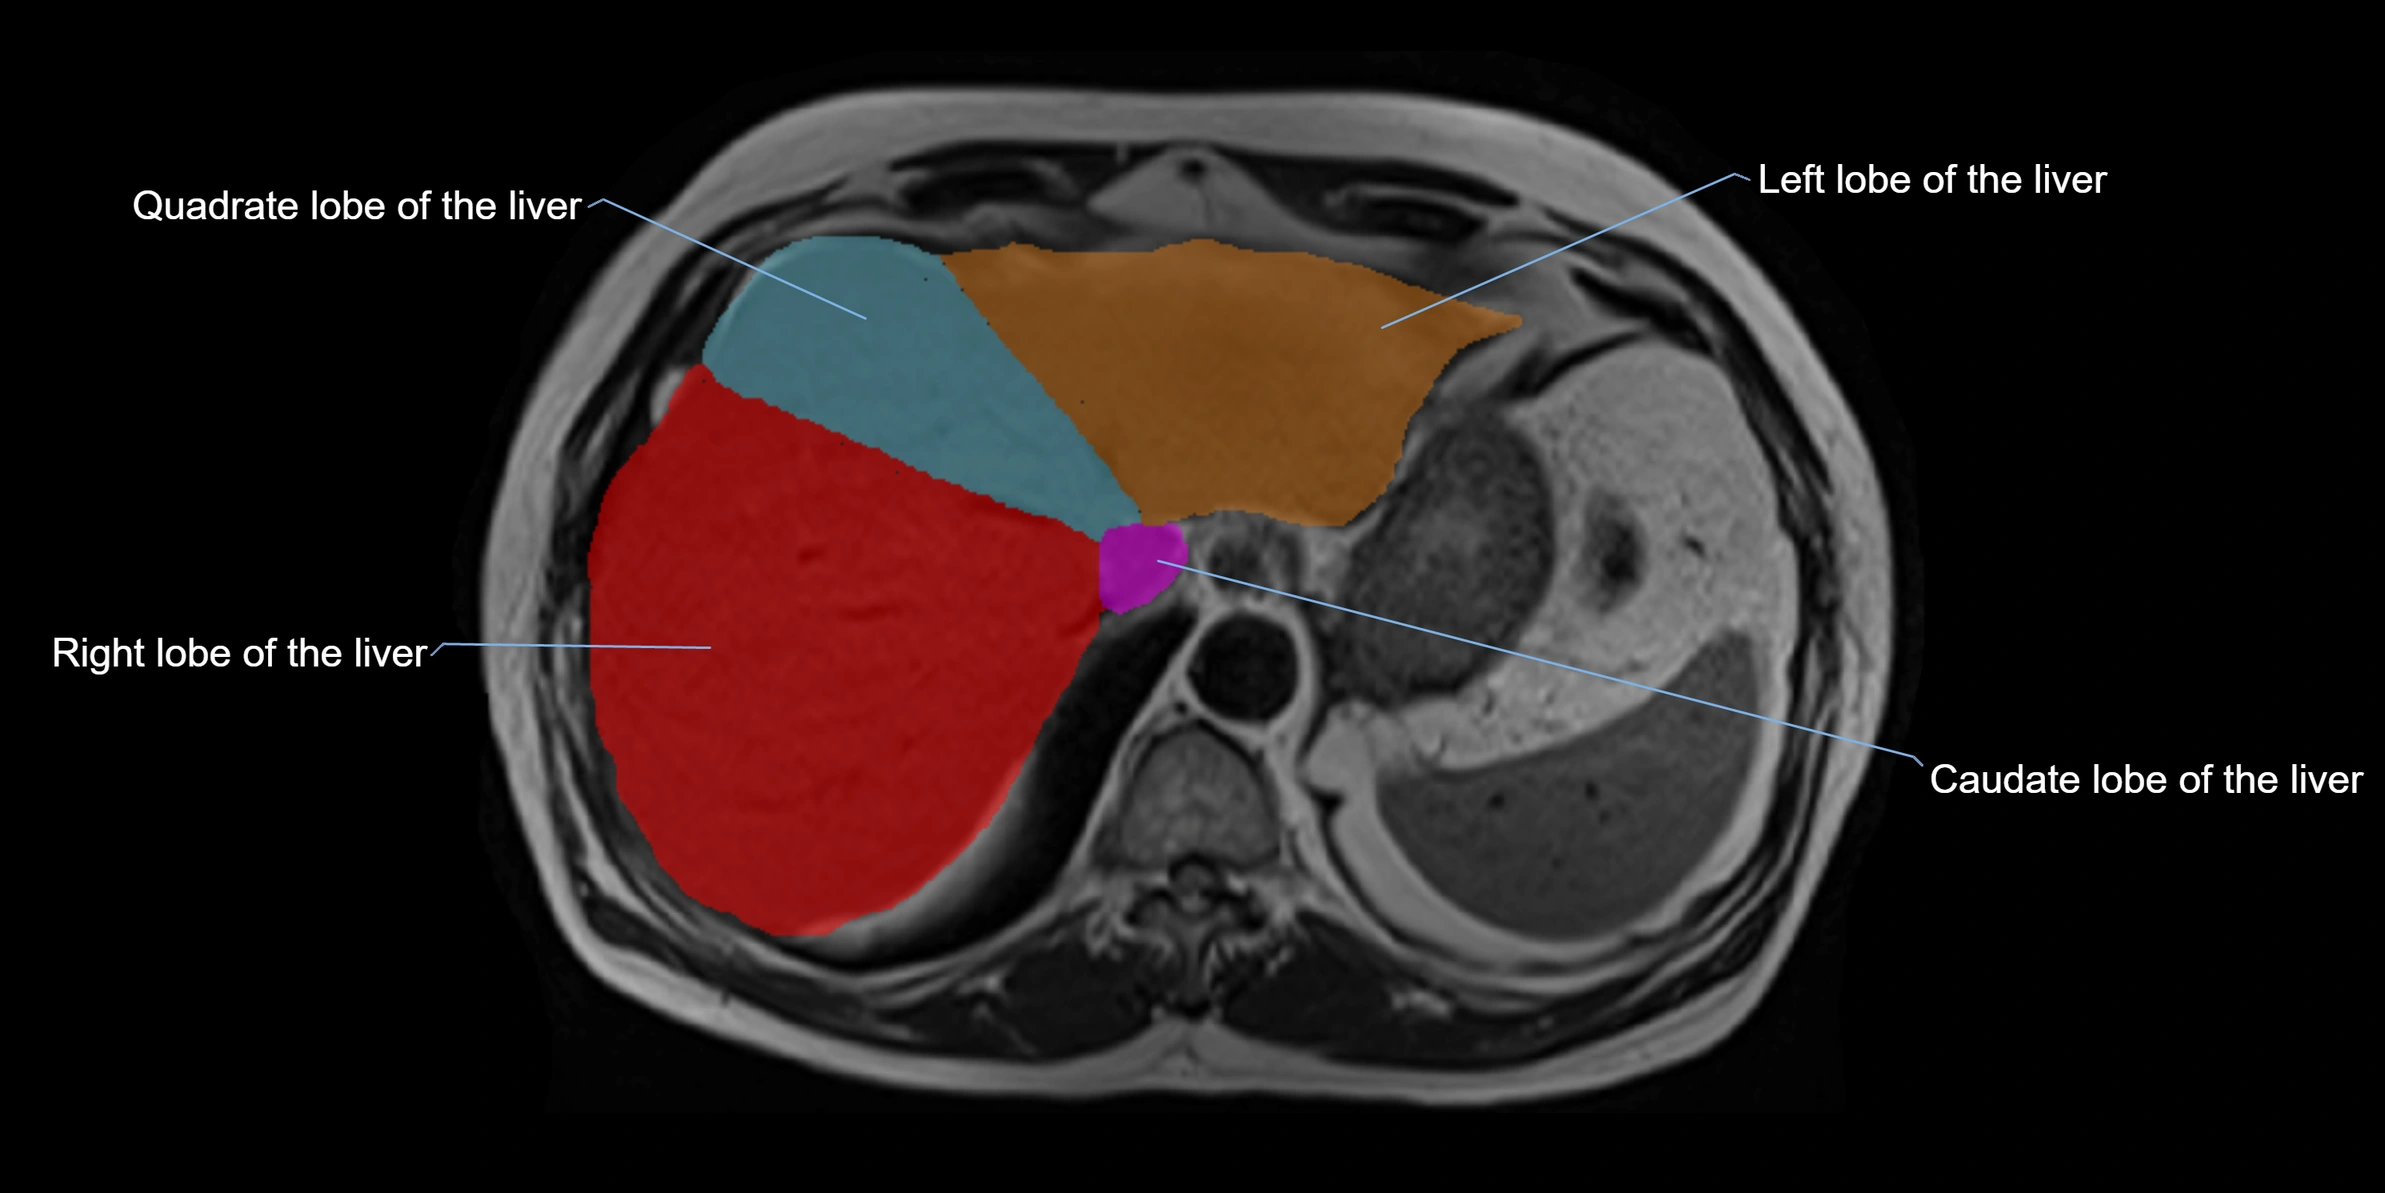

The caudate lobe of the liver is a distinct anatomical subdivision of the liver, designated as segment I in Couinaud’s classification. It lies on the posterior surface of the liver, between the fissure for the ligamentum venosum (left boundary) and the groove for the inferior vena cava (IVC) (right boundary). Superiorly, it is related to the posterior liver surface, and inferiorly it is separated from the left lobe by the porta hepatis.

The caudate lobe is unique because it receives dual portal venous and arterial inflow from both the right and left portal veins and hepatic arteries. It also has independent venous drainage directly into the IVC via multiple small hepatic veins, unlike other lobes that drain through the three main hepatic veins.

This anatomical autonomy makes the caudate lobe especially significant in liver surgery, transplantation, and hepatic venous outflow obstruction syndromes (e.g., Budd–Chiari syndrome). Enlargement of the caudate lobe is a characteristic imaging feature in chronic liver disease and cirrhosis.

• Enlargement may be appreciated in cirrhosis or Budd–Chiari syndrome

• Caudate lobe often enhances relatively more than other lobes in Budd–Chiari syndrome, due to preserved venous outflow